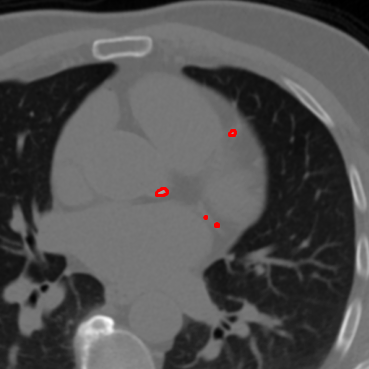

The effectiveness of our label-guided approach is visualized in Figure 4, which compares feature representations generated by standard DINO and DINO-LG models via PCA analysis. The figure shows an original CT slice containing coronary calcification in the left anterior descending artery (a), where the ground truth annotation (b) occupies approximately 0.04% of the image area. Standard DINO features (c) exhibit diffuse activation across cardiac structures, while DINO-LG features (d) demonstrate concentrated activation on calcified regions (bright yellow areas), validating successful feature guidance toward regions of clinical interest. The PCA visualization is applied to 768-dimensional [CLS] token embeddings extracted from the final transformer layer to illustrate how label-guided training directs the model’s attention to task-relevant features.

(a)

(b)

(c)

(d)

Figure 4: Feature visualization comparison via PCA. (a) Original CT slice. (b) Ground truth annotation. (c) Standard DINO features. (d) DINO-LG features.